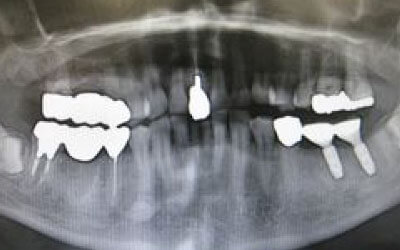

今回のご質問ですが、抜けた部分の骨が薄いなどの理由で「インプラントはできない」と言われた可能性があります。

前歯はもともと骨が薄く、歯が抜けると時間の経過とともにさらに骨が痩せてきてしまうので、インプラント治療の難易度が高い場所です。

ただ結論からお話すると、インプラント治療は可能です。

なぜなら、もし仮に骨が薄くても、骨の治療によって厚みが増せば、安全にインプラント治療が行えるからです。

1)インプラント治療を行う前に、骨の治療が必要かもしれません。

2)骨の治療から始めると、その分、治療期間が長くなります。

3)骨の治療は、通常のインプラント治療よりも難易度が高いため、経験の豊富な先生やインプラント認定医のいる歯科医院で治療を受けることをお勧めします。

4)骨の状況をしっかり把握するためにも、CT撮影が必須となります。